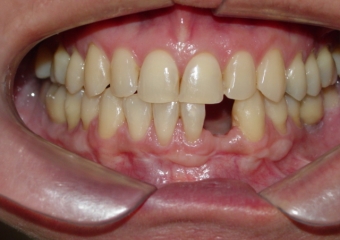

Imagem após extração do dente 32, devido a reabsorção radicular